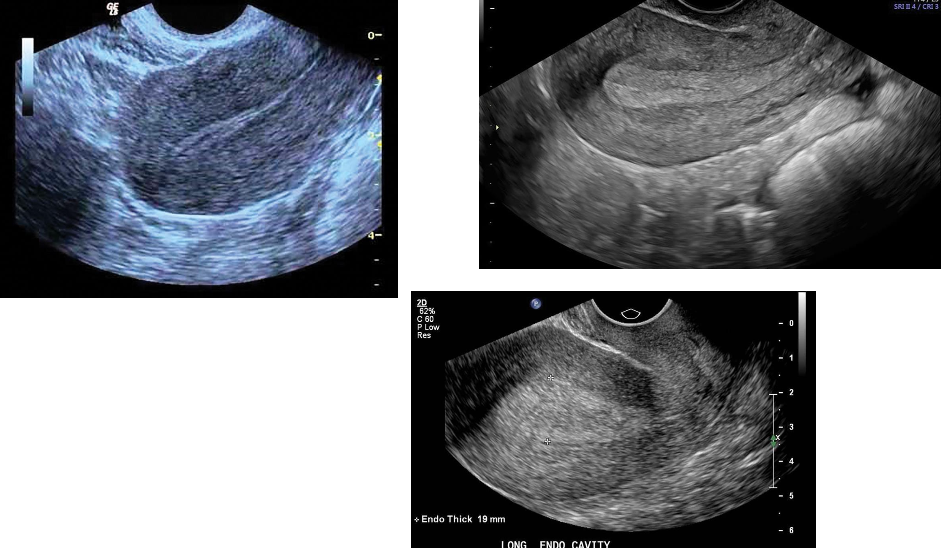

___________is the most common gynecologic malignancy in North America, and its

incidence has been rising.

Most endometrial malignancies are adenocarcinomas occurring in postmenopausal patients.

The most common clinical presentation is uterine bleeding, although only 10% of women with

postmenopausal bleeding will have endometrial carcinoma.

There is a strong association with replacement estrogen therapy.

In the premenopausal woman, anovulatory cycles and obesity are also considered risk factors.

The earliest change of endometrial carcinoma is a thickened endometrium. An abnormally thick

endometrium is also associated with endometrial hypertrophy and polyps.

Although increased endometrial thickness is an early finding in endometrial carcinoma,

enlargement with lobular contour of the uterus and mixed echogenicity are correlated with

more advanced stages of the disease. The risk of malignancy increases with the presence of a

large endometrial fluid collection or clinical symptoms, such as abdominal pain or bleeding.

Endometrial carcinoma may obstruct the endometrial canal, resulting in hydrometra or hematometra.

The level of myometrial invasion (superficial versus deep) also can be detected by transvaginal ultrasonography, although

contrast-enhanced MRI is more sensitive. MRI is also valuable in evaluating extrauterine extension and involvement of

lymph nodes.

Sonographic Findings

Transvaginal examination is helpful in screening for early changes of endometrial hyperplasia or carcinoma

by accurately measuring endometrial thickness.

Sonographically, a thickened endometrium (greater than 4 to 5 mm, and this value varies institution to

institution) should be considered cancer until proven otherwise.

Demonstration of myometrial invasion is clear evidence for endometrial carcinoma.

Transvaginal ultrasonography demonstrates myometrial invasion as thickening and irregularity of the central

endometrial interface with echogenic or hypoechoic patterns combined with infiltration of hyperdense structures

in the myometrium.

Cystic changes within the endometrium are more commonly seen in endometrial atrophy, hyperplasia, and polyps

but can also be seen with carcinoma.

Endometrial masses containing numerous vascular branches with color imaging should also raise the level of

suspicion for carcinoma.

Endometrial Carcinoma